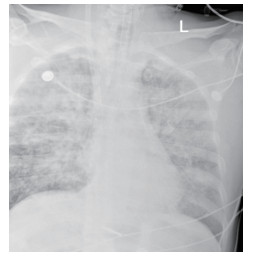

1.2 临床表现和检查患者初期有咳嗽症状,但未在意,患者回家24 h后咳嗽症状加重,伴胸闷气喘,全身大汗淋漓,家属立即将其送至本院急诊,为进一步诊治拟“有机氟中毒”收住入院。入院时体检:神志清楚,T:36.5℃,R: 57次/min,BP: 146/71 mmHg,胸廓对称无畸形,呼吸急促,听诊双肺呼吸音清晰,可闻及大量湿性啰音,心率112次/min,心律齐,心音正常,各瓣膜听诊区未闻及病理性杂音及心包摩擦音,四肢关节正常,双下肢无水肿,深浅生理反射正常,病理反射阴性,脑膜刺激征阴性。辅助检查:白细胞计数10.45×109/L,中性粒细胞91.9%;C-反应蛋白14.81 mg/L, 无创机械通气支持下血气分析pH7.28,PCO2 50 mmHg, PO2 57 mmHg, Lac 3.0 mmol/L(FiO2 50%),为Ⅱ型呼吸衰竭,给予无创呼吸机辅助呼吸、激素冲击、解痉平喘等抢救治疗。急诊胸部CT检查提示:两肺散在斑片状模糊影,密度不均,边界不清(图 1),进ICU床边胸片提示:两肺散在斑片状模糊影(图 2)。根据GBZ5—2016《职业性氟及其无机化合物中毒的诊断》的诊断标准,该患者诊断为职业性急性重度有机氟中毒。

| 图 1 3月10日胸部CT |